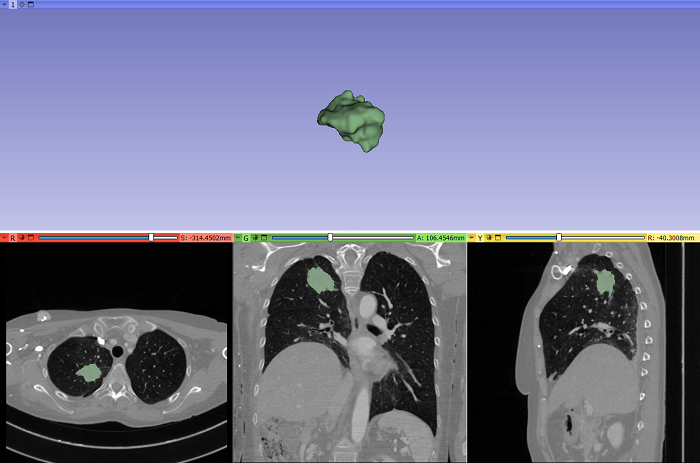

Gracias a este estudio, se ha identificado un biomarcador no invasivo para predecir el beneficio clínico duradero de la inmunoterapia, basado en la integración de datos radiómicos y clínicos monitorizados, durante los primeros meses de tratamiento con anticuerpos monoclonales anti-PD-1/PD-L1, en pacientes con cáncer de pulmón no microcítico avanzado.

La identificación de biomarcadores predictivos no invasivos de la respuesta a la inmunoterapia es crucial para evitar interrupciones prematuras del tratamiento o prolongaciones ineficaces. Un biomarcador se utiliza a veces para determinar la respuesta del cuerpo a un tratamiento para una enfermedad o afección.

La inmunoterapia se ha convertido en uno de los tratamientos de referencia del cáncer de pulmón avanzado no microcítico, con tasas de respuesta prometedoras, enfermedad que sigue presentándose con una frecuencia alta. La predicción de la eficacia de la respuesta al tratamiento antes y durante el tratamiento, sigue siendo crítica para el manejo personalizado de los pacientes.